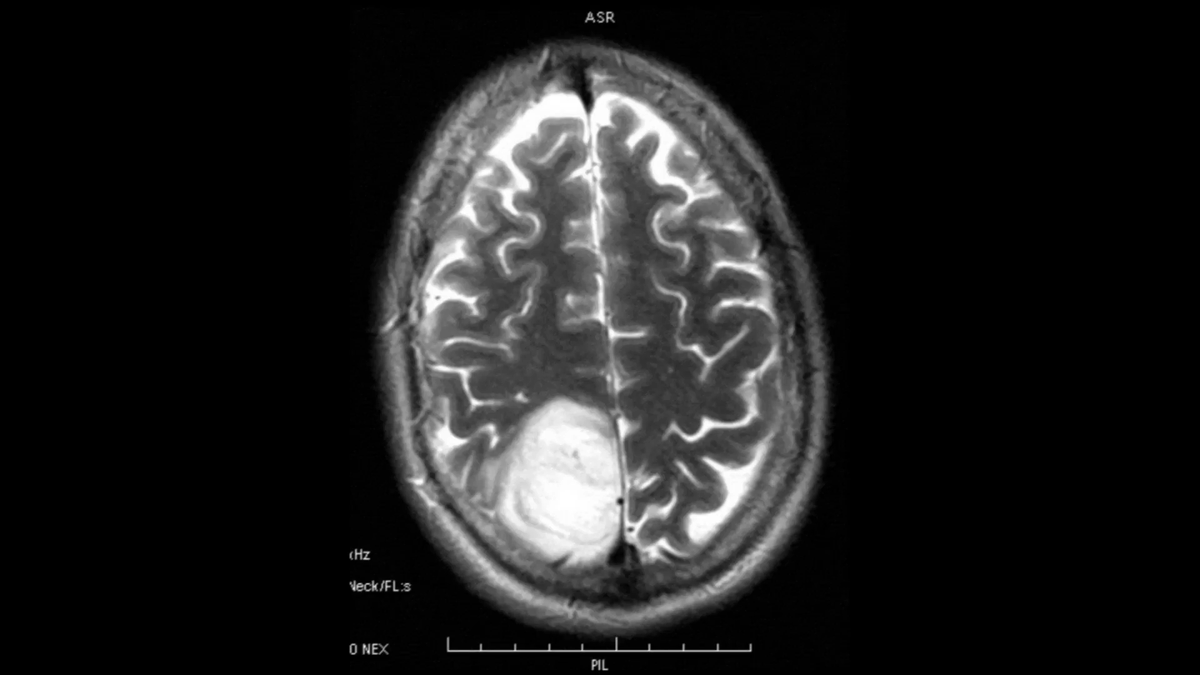

النتائج كشفت عن وجود كتلة في الفص الجبهي الخلفي الأيسر بالقرب من الجافية، وهي تتوافق مع ورم سحائي، وهو نوع من أورام الدماغ.